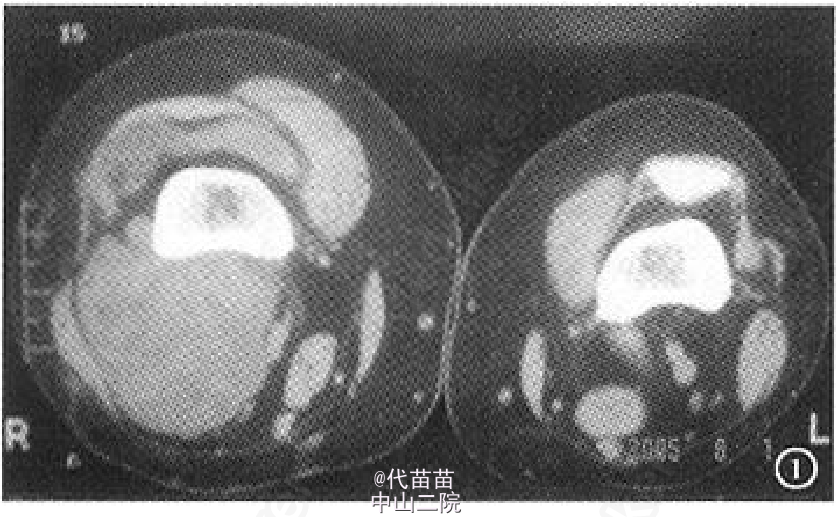

患者,女,70岁 。主因右膝关节间断性疼痛4年,加重2个月入院。患者自诉4年前无明显诱因出现膝关节间断性疼痛,活动时疼痛加重,休息后症状缓解,同时伴有右膝关节肿胀,膝关节活动时弹响症状明显,无夜间痛,未系统治疗。近2个月来患者疼痛症状逐渐加重,不能完全蹲下,并出现右小腿轻度肿胀。患者既往体健。查体:右膝关节肿胀,无发红及包块。右膝关节间隙按压痛阳性,浮髌试验阳性,髌骨摩擦试验阳性,右膝关节活动度:0°~130°,右下肢肌力Ⅳ级,其他检查未见异常。 影像学检查:X 线片示右侧膝关节不对称性变窄,关节面硬化,边缘可见唇样骨质增生,股骨下端凹槽样改变,边界较清楚,无骨膜反应,髌骨呈槽沟样改变(图 1a)。 右膝关节 CT 示右侧髌骨较薄,髌骨关节面锯齿样改变(图 1b)。MRI检查示膝关节腔内液体增多髌上囊内可见低信号影(图 1c)。为排除肿瘤及感染的可能性,进一步行实验室检查:血常规、ESR、CRP 及碱性磷酸酶以及 ECG 检查均未见异常。完善相关检查后, 择期行全膝关节表面置换术及滑膜清理术。为防止术后股骨缺损处出现病理性骨折,考虑选用制定型膝关节假体(股骨假体柄加长)。术中见:膝关节髌上囊内有大量陈旧性积血(图 1d),滑膜增生肥厚,股骨远端髁部上段可见轮廓清楚的凹陷性骨侵蚀面,股骨及胫骨骨赘形成,股骨髁及胫骨平台关节面软骨破坏,股骨外侧髁破坏严重,部分软骨下骨外露, 髌骨外侧变薄, 髌骨关节面有沟槽样凸凹不平(图1d),软骨面破坏,外侧较重,软骨下骨外露。 术中将病变关节囊及滑膜送检病理,快速病理回报:色素绒毛结节性滑膜炎可能性大。 术中彻底切除髌上囊、滑膜、髌下脂肪垫及半月板,切除胫骨表面、前十字韧带及后十字韧带,处理股骨髁,矫正 FTA 角为外翻 5°,安装 Depuy 公司 2 号股骨假体加长柄及2 号胫骨假体,胫骨假体上安装 8 mm 垫片,复位关节。检查内外侧软组织平衡良好,功能活动良好,此时行髌骨成形术,修理髌骨后见髌骨活动轨迹差, 缝合前向关节腔内软组织注入镇痛药物。 术后右侧膝关节侧位片示:假体固定位置良好,股骨加长柄通过股骨皮质缺损区(图 1e)。 术后病理诊断:色素绒毛结节性滑膜炎(图 1f)。 术后 24 h 拔除负压引流,伸直位